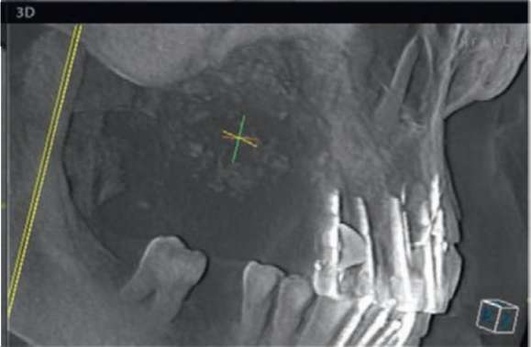

Хроническое воспаление верхнечелюстной пазухи, как правило, развивается при переходе острого воспаления в хроническое, но возможно и без предшествующей ярко выраженной острой стадии заболевания. Пациенты жалуются на боли и чувство тяжести в затылочной области, однако у многих пациентов заболевание протекает, в принципе, бессимптомно, за исключением периодических эпизодов нарушения носового дыхания (рис. 5.86, 5.87).

image

Рис. 5.86. .Хронический одонтогенный верхнечелюстной синусит слева

Рис. 5.87. Хронический одонтогенный верхнечелюстной синусит слева. Инородное тело верхнечелюстной пазухи (корень зуба).